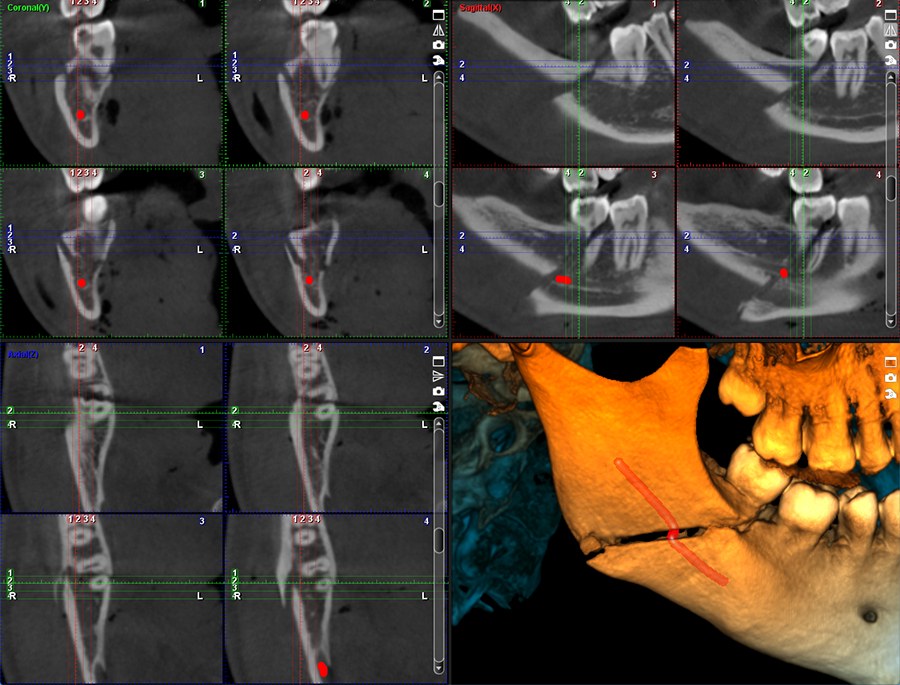

4 yếu tố có thể xác định chất lượng phim chụp:

• Grayscale: là phạm vi các sắc thái xám giữa trắng và đen. Trong X-quang, các sắc thái xám khác nhau cần phải được phân biệt rõ ràng để có thể nhìn thấy tốt các chi tiết.

• Gamma Correction: là cách tối ưu hóa việc sử dụng các bit trong hình ảnh để cho ra ánh sáng và màu sắc trung thực. Nếu không có hiệu ứng gamma, hình ảnh sẽ khác so với những gì chúng ta dự đoán – quá tối hoặc quá sáng, bị trôi, lệch màu,…

• Lumen (độ sáng): 1 bức ảnh chụp đủ độ sáng sẽ giúp xem được rõ ràng và chi tiết hơn.

• Resolution (Độ phân giải): liên quan đến voxel trên một thể tích ảnh, số lượng voxel càng nhiều, voxel càng nhỏ thì ảnh 3D càng rõ nét.